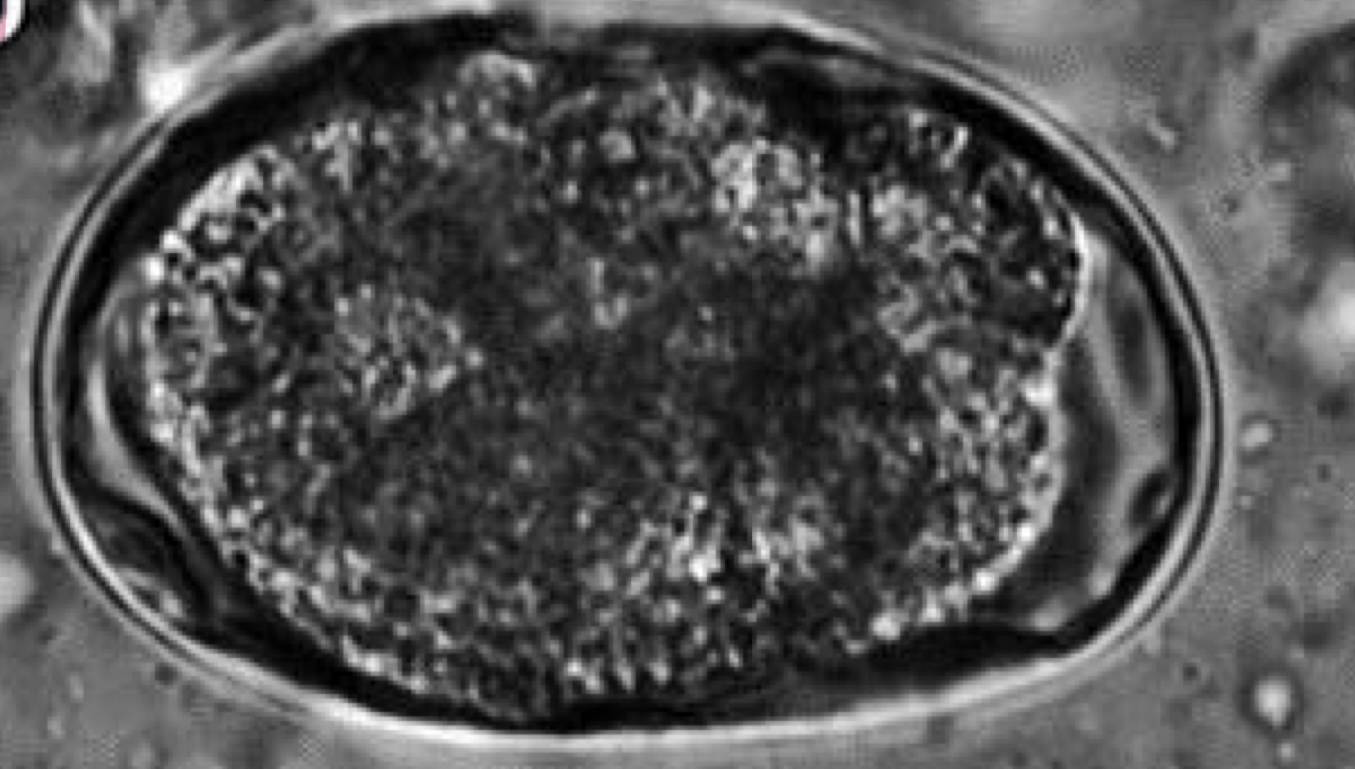

Characteristics of Strongyloidea (Ancylostoma) species

PPP - depends of species and route of transmission

route of transmission: ingestion of eggs, transdermal, across placenta/mammary milk

Dx: fecal flotation

attach to small intestine of cats, dogs and large animals

produce severe anemia in kittens and puppies

ZOONOTIC

eggs:

oval or ellipsoid, thin walls with 8-16 cells

larvate rapidly in environment (fresh feces needed)

prevention: interceptor, heartguard

treatment: mebendazole, fenbendazole